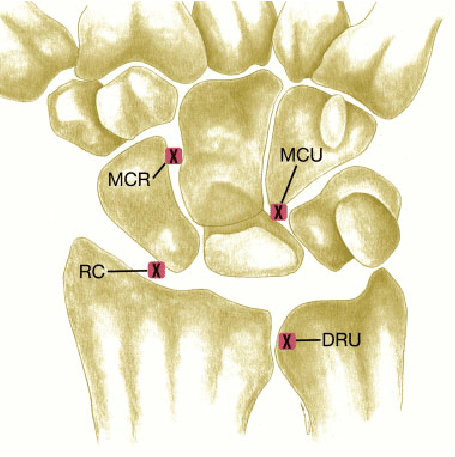

2. 해부학

- 손목에 작은 뼈들은 8개로 구성되어있습니다.

- 근위열 4개뼈

- 주상골(scaphoid), 월상골(Lunate), 삼각골(Triquetrum), 두상골(Pisiform)

- 원위열 4개뼈

- 대능형골(Trapezium), 소능형골(Trapezoid), 유두골(Capitate), 유구골(Hamate)

- 손목을 이루는 모든 관절에서 발생할 수 있습니다. 특히 주상골(Scaphoid)와 관련되어서 많이 발생하게 됩니다. 거의 손목의 관절염에서 90%이상이 주상골과 관련되어 있다고는 연구도 있습니다.

- 앞서 말했듯 퇴행은 주상골주변에서 가장 많이 발생합니다.

- 보통 처음에는 요골경상골기(Radial styloid)와 주상골의 닿는 부분에서 관절염이 우선 발생되고 이 후 주변 관절로 침범하게 됩니다.